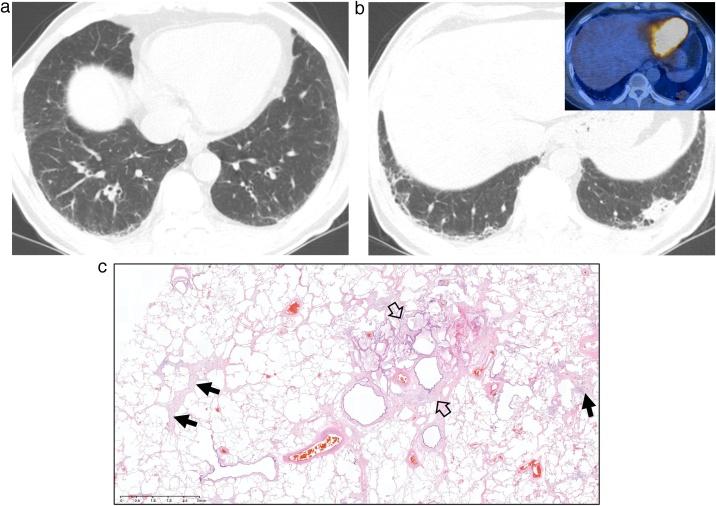

间质性肺异常(ILA)和非特异性间质性肺炎(NSIP)。

Interstitial lung abnormality (ILA) and nonspecific interstitial pneumonia (NSIP).

This review article aims to address mysteries existing between Interstitial Lung Abnormality (ILA) and Nonspecific Interstitial Pneumonia (NSIP). The concept and definition of ILA are based upon CT scans from multiple large-scale cohort studies, whereas the concept and definition of NSIP originally derived from pathology with evolution to multi-disciplinary diagnosis. NSIP is the diagnosis as Interstitial Lung Disease (ILD) with clinical significance, whereas only a part of subjects with ILA have clinically significant ILD. Eventually, both ILA and NSIP must be understood in the context of chronic fibrosing ILD and progressive ILD, which remains to be further investigated.

这篇综述文章旨在探讨间质性肺异常(ILA)和非特异性间质性肺炎(NSIP)之间存在的奥秘。ILA的概念和定义基于多项大规模队列研究的CT扫描结果,而NSIP的概念和定义最初源自病理学,并逐渐发展为多学科诊断。NSIP是具有临床意义的间质性肺疾病(ILD)诊断,而只有一部分ILA患者患有具有临床意义的ILD。最终,ILA和NSIP都必须在慢性纤维化ILD和进行性ILD的背景下理解,这仍有待进一步研究。